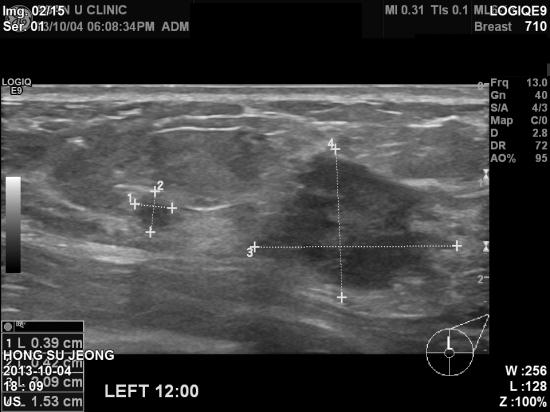

병원에서 꾸준히 유방암 정기검진 받으시던 분으로

출산 후 모유 수유와 육아문제로 2~3년정도

검사못하고 지내다가

만져지는 몽우리가 2일전에 갑자기

생겨

내원하여 초음파 검사를 하신

43

여자분이십니다

.

조직검사를 시행하여 침윤성 유관암으로

진단되셨습니다